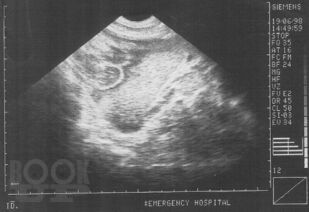

В монографии изложены основные достижения в диагностике закрытой травмы живота, приведены методики УЗИ с описанием эхосемиотики повреждений различных органов брюшной полости и забрюшинного пространства. Включены клинические примеры и большой иллюстративный материал, полученные в процессе собственных исследований. Приведен и аргументирован разработанный на кафедре госпитальной хирургии ВолгГМУ алгоритм диагностики и лечения сочетанной закрытой травмы живота, что определяет выраженную практическую направленность данной рукописи. Монография представляется весьма ценной для студентов старших курсов лечебных факультетов медицинских вузов, клинических ординаторов, практических врачей.